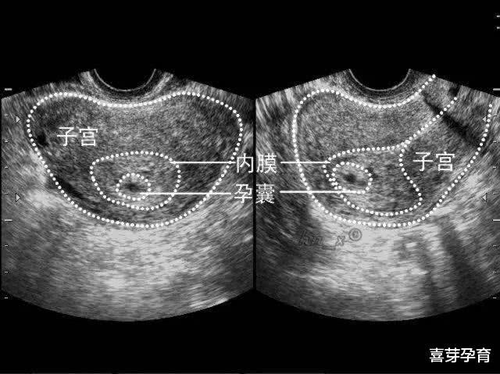

子宫附件出现的囊性结构比较常见的就是卵巢囊肿了。具体发病的原因还不是很明确,一般认为与女性体内激素代谢有关。囊肿的大小不同,质地不同,具体治疗的方式不同。可以通过彩超或者是ct,查看囊肿大小,数量,性质等。如果囊肿没有超过5cm,可以通过中药进行治疗。如果超过5cm,多会选择手术治疗。